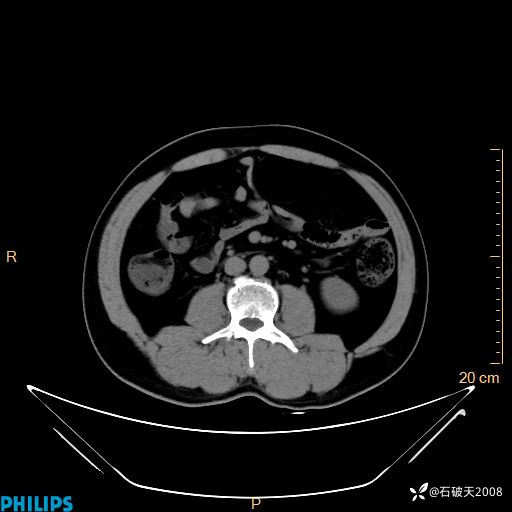

增强轴位